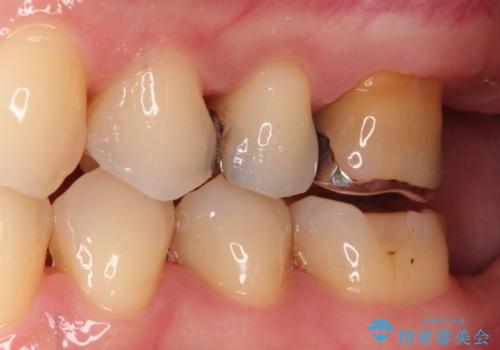

装着したセラミックインレーは、隣り合う天然歯と見分けがつかないほど自然な色調と透明感を再現しています。また、セラミックはプラーク(歯垢)が付着しにくく、適合性が非常に高いため、二次的な虫歯の予防にも大きく貢献します。

お口を開けた際に目立っていた銀色の部分が解消され、清潔感のある明るい口元になりました。金属アレルギーの心配もなく、健康的で美しい状態を長期的に維持することが可能です。